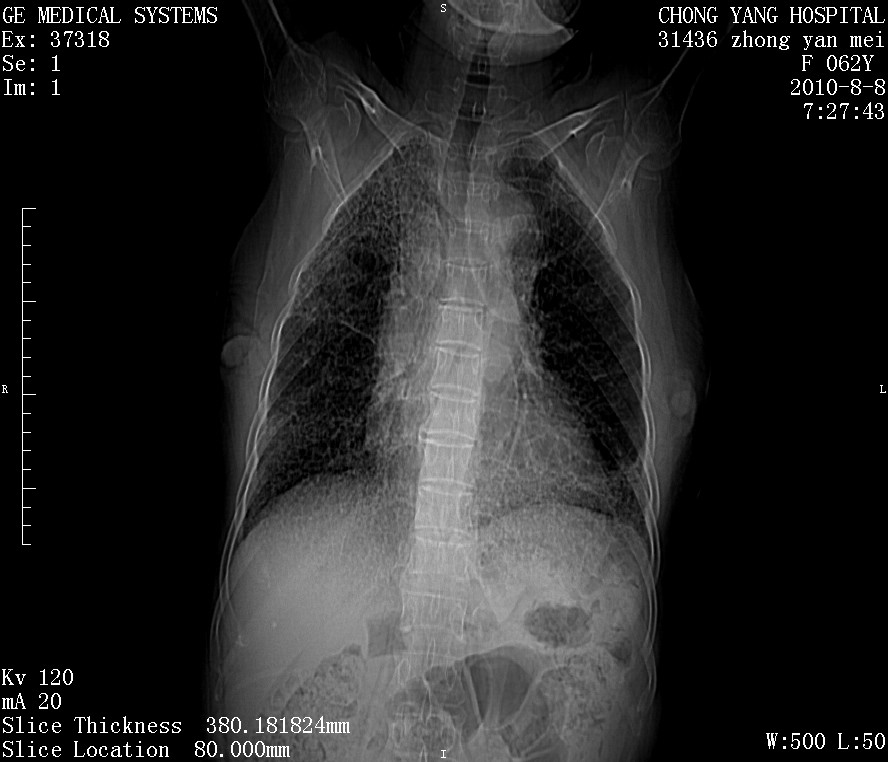

标题: CT28269:F62Y咳嗽胸痛数月。 [打印本页]

标题: CT28269:F62Y咳嗽胸痛数月。

作者: dr.yang    时间: 2010-8-9 02:34

两肺弥漫性间质纤维化伴继发性支扩。

另见右乳腺似有小钙化灶,建议进一步检查。